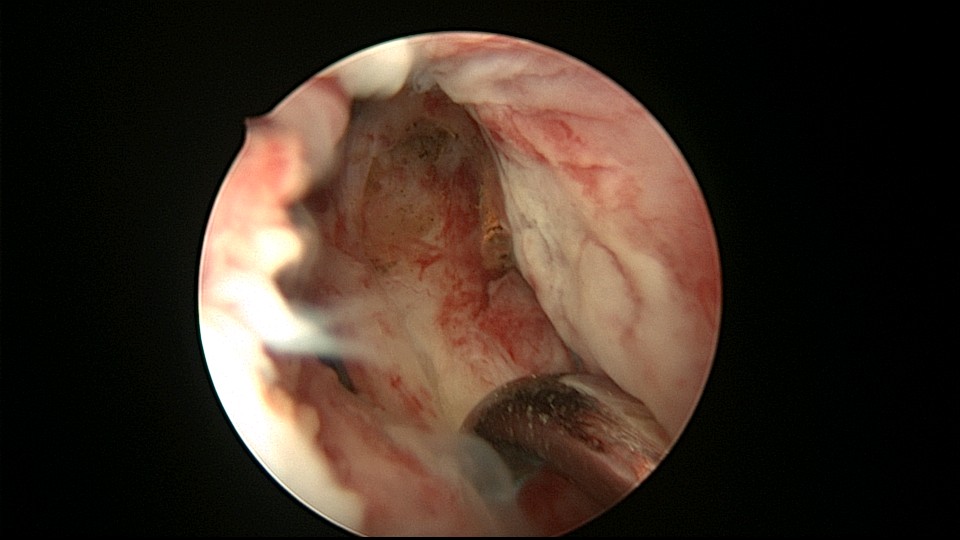

患者48岁,G3P1,顺产1次。安环10年,绝经1年,外院取环失败,子宫穿孔,腹部平片无异常。宫腔镜见宫腔广泛致密粘连,V型环与粘连组织嵌顿,取环钩盲视下多次尝试钩取节育环,均失败。取环钩循镜鞘外侧进入宫腔,直视下钩住节育环,顺利取出。再次置镜寻找子宫穿孔处并进入盆腔,见网膜脂肪组织,确认无活动性出血及盆腔积血,结束手术。